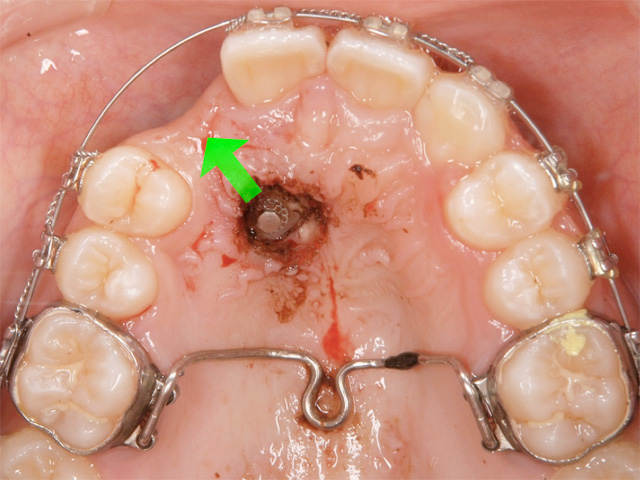

お口の天井部分を麻酔して開き、犬歯にフックをつけて矯正装置を用いて適正な位置まで移動させました。